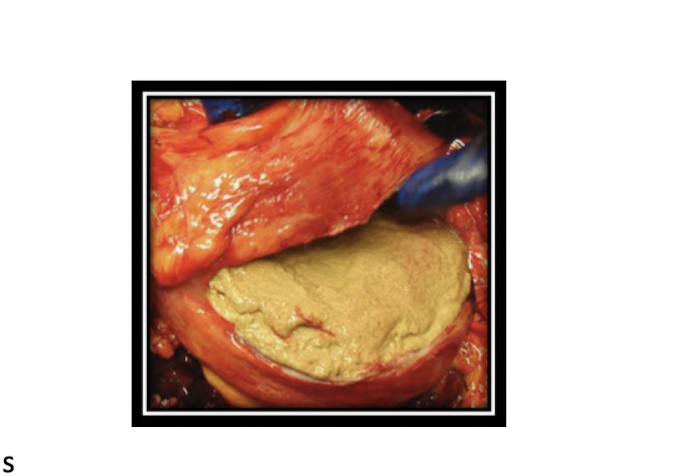

Cystotomy

-Bladder will sit in the pelvic inlet: gentle traction to exteriorize. Saline to distend if desired and let it out right before bringing the stone out, makes it easier to exteriorize

-Peel the mucosa off the stone, tightly adhered to spicules

-Lavage bladder: any pieces left can cause new stone formation